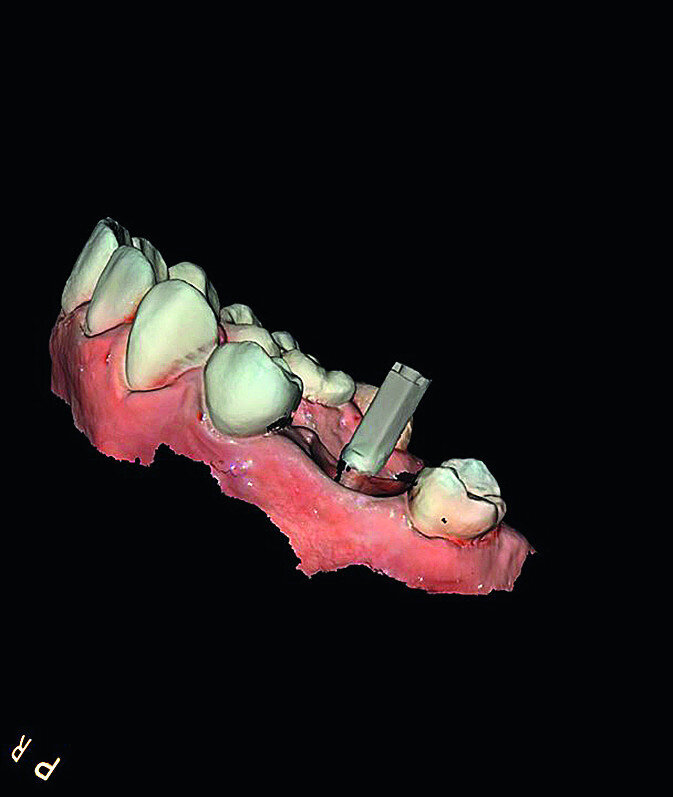

In March 2018, four months after the surgery, the prosthetic phase was started. An impression was taken with an intraoral scanner (CS 3600, Carestream Dental) using scan bodies for an impression at the implant head (MegaGen; Figs. 11a & b). The information was sent to the Anatomic Lab, where a crown was designed using a CAD programme. After the design of the crown had been finished, the information was sent to a milling machine (Amann Girrbach) and the crown was milled (Fig. 12). One week after the preparation, the definitive crown in monolithic zirconia was attached and the occlusion tested using T-Scan technology (Tekscan; Figs. 13a–c & 14).

Nowadays, we also have the possibility to superimpose the information related to the teeth and gingivae, received from the intraoral scan, over the bone-related information acquired with CBCT. It is therefore possible to plan the optimal positioning of implants with software to guide the surgery. Planning data is transferred to a surgical template that can be physically fabricated in various ways and with different materials. This guide will help the surgeon correctly position the implants without needing to raise a flap. [18]